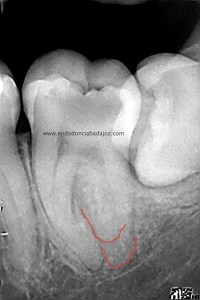

Después de haber instrumentado con un sistema Protaper, y habiendo estandarizado el conducto en un 25mm en apical y una conicidad del 6% con limas K3. observé que el conducto Distal presentaba otro conducto Disto-Vestibular cuya entrada estaba en la pared del conducto Disto-Lingual tratado, bastante complicado de trabajar.

Observando la Rx pude verificar y diferenciar las raices: